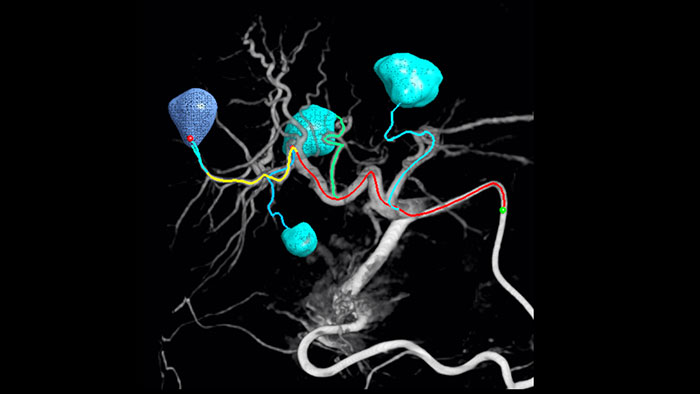

Automatic Feeder Detection solution can significantly improve feeding artery detection. EmboGuide supports you in maximising the efficacy of your TACE procedures as it potentially enhances your sensitivity, reduces false positives and maximises inter-reader agreement1. EmboGuide also provides efficient, workflow-based live 3D guidance with automatic feeder detection1.

Adoption of chemo/radioembolisation techniques such as TACE and SIRT drives the need for standardisation and efficiency. Case after case, you must reliably and consistently locate the tumor(s), identify all feeder vessels, and plan/execute the appropriate interventional approach. Our Automatic Feeder Detection solution can significantly improve feeding artery detection compared to using Cone Beam CT alone. EmboGuide supports you in maximising the efficacy of your TACE procedures as it potentially enhances your sensitivity, reduces false positives and maximises inter-reader agreement.1

The ability to detect and differentiate hepatic nodules and identify tiny feeder vessels is critical to determining proper therapy. Navigating to the region of interest by reaching all feeders, while remaining selective to the lesion, increases the opportunity for success. Confirmation of treatment endpoint and treatment success while the patient is still on the table boosts clinical outcome confidence.